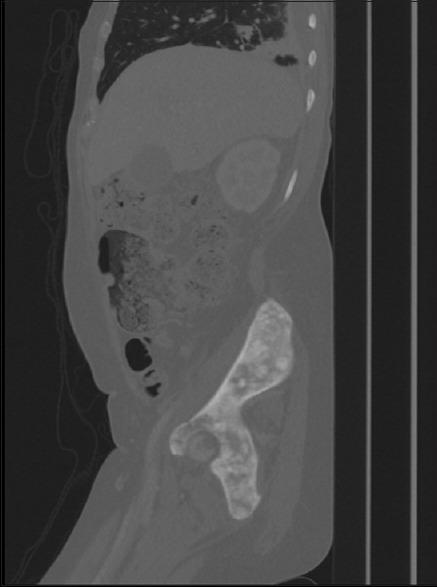

Cholangiocarcinoma (CCA) is a rare cancer of the bile duct epithelial cells and it commonly spreads to the regional lymph nodes, liver, and lungs. Bone metastasis has been reported in patients with CCA, involving both the axial and appendicular skeleton. Herein, we report a case of extrahepatic CCA with extensive bone metastases involving the calvarium, sternum, bilateral ribs and scapulae, entire spine, pelvis, and bilateral femur. To our knowledge, this is the first case report on sternum metastasis in CCA. The case presentation and review of literature highlighted the rarity of this metastasis, and health-care providers should be aware of the rare presentation of CCA.

胆管癌(CCA)是一种罕见的胆管上皮细胞癌,通常会扩散至区域淋巴结、肝脏和肺部。已有CCA患者发生骨转移的报道,累及中轴骨和四肢骨骼。在此,我们报告一例肝外CCA患者,其发生广泛骨转移,累及颅骨、胸骨、双侧肋骨和肩胛骨、整个脊柱、骨盆及双侧股骨。据我们所知,这是首例关于CCA胸骨转移的病例报告。该病例介绍及文献回顾突出了这种转移的罕见性,医疗保健人员应了解CCA的这种罕见表现。